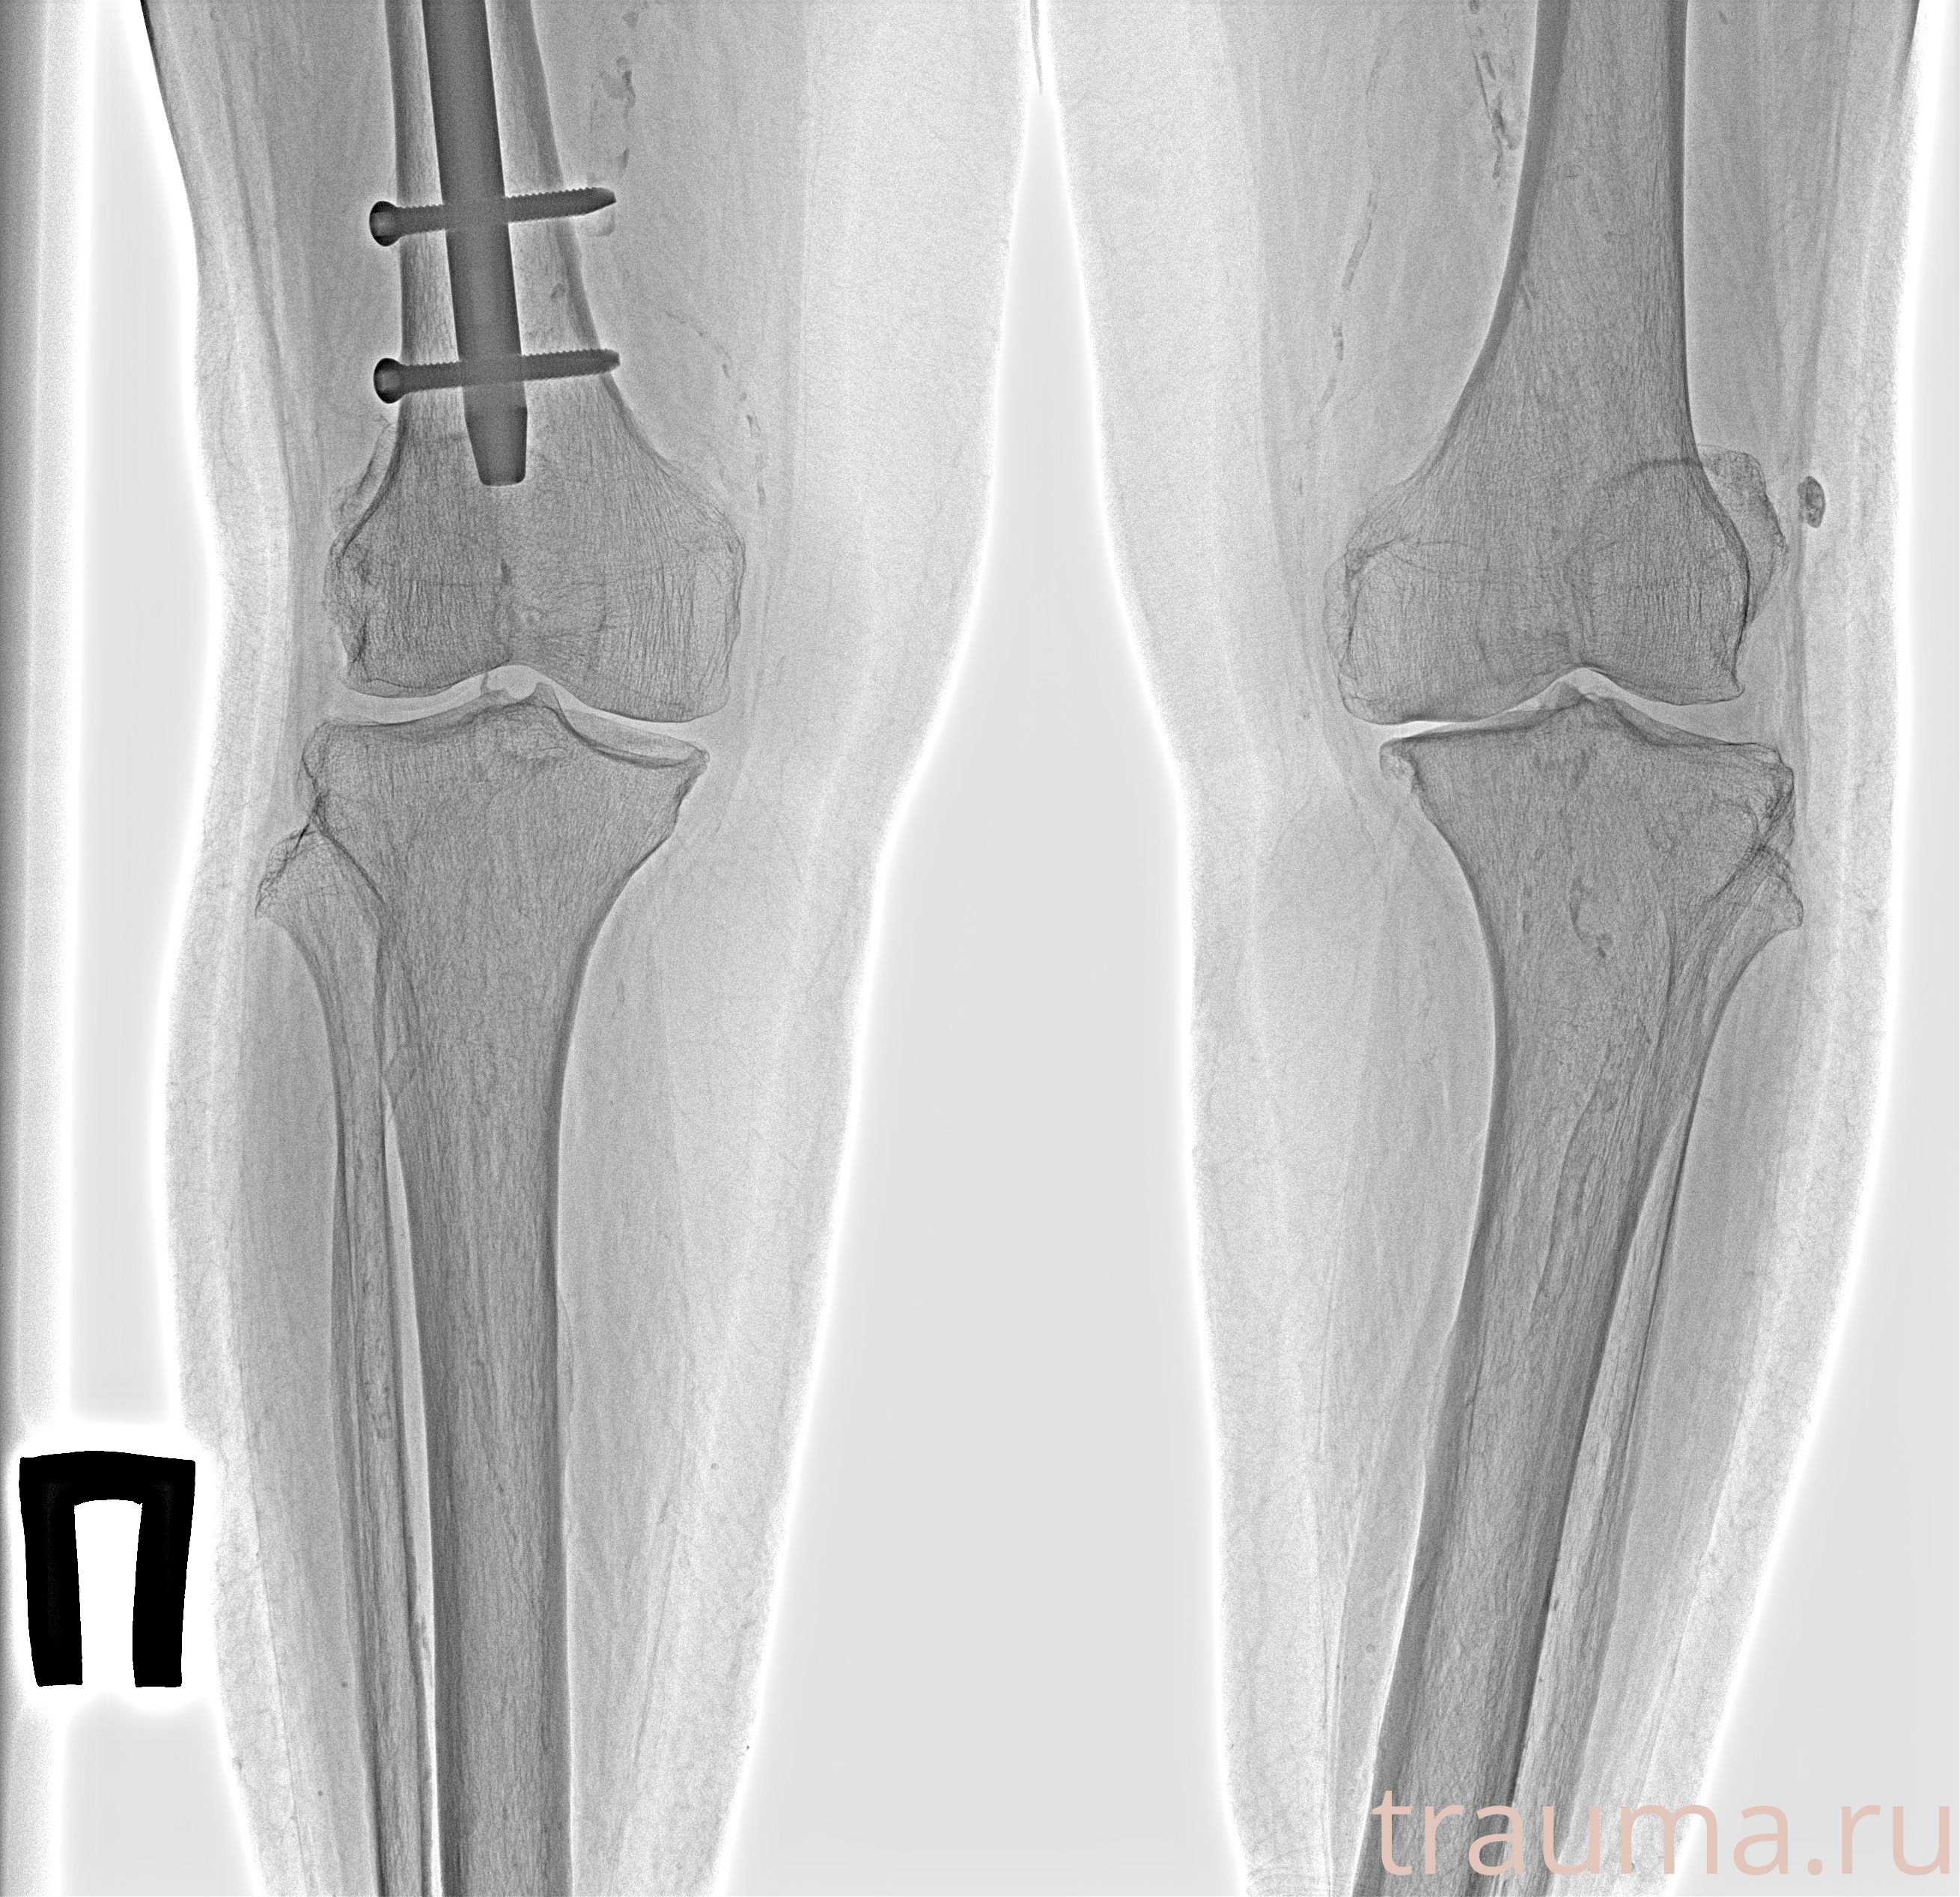

Рентгенограммы